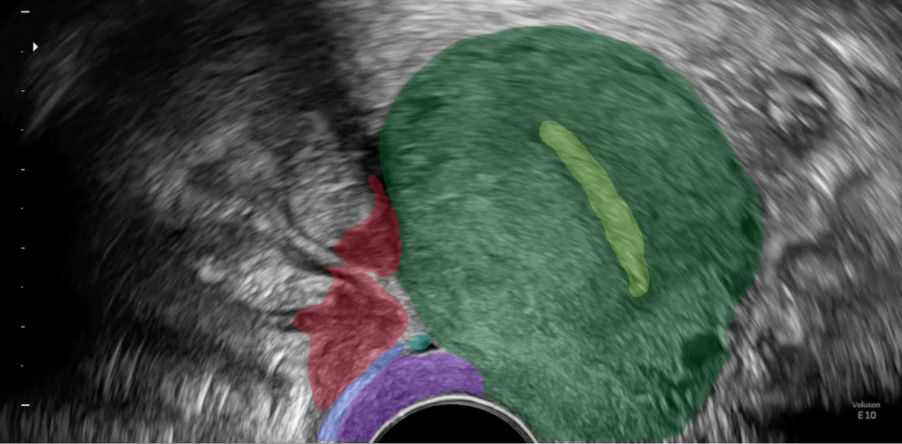

Expert AI competence for real-time ultrasound analysis and user guidance

Endometriosis may present as nodules or adhesions. Adhesions stick together organs like the uterus, ovaries, and bowel. These are very difficult to detect but have to be diagnosed when mapping the individual spread of endometriosis. At Scanvio we are establishing a new medical standard for ultrasound-based diagnosis of endometriosis which will be directly implemented into our product.

The Scanvio AI Assistant™ will enhance ultrasound examinations by providing live feedback on image quality and organ exposure, ensuring optimal imaging conditions and offering comprehensive feedback on probe orientation and investigated areas. This facilitates the visualization of pathologies, enabling precise disease mapping and severity estimation, which are crucial for personalized treatment and surgical planning.